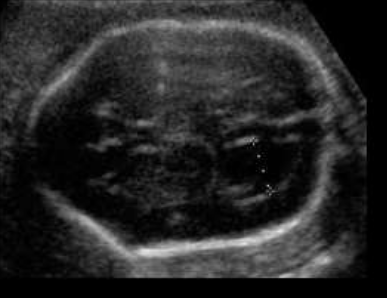

Paciente 24 anos, secundigesta, apresentando idade gestacional de 23 semanas, gestação não planejada, encaminhada para avaliação morfológica do segundo trimestre.

Após analisar as imagens abaixo, quais os sinais ecográficos encontrados e qual a hipótese diagnóstica?